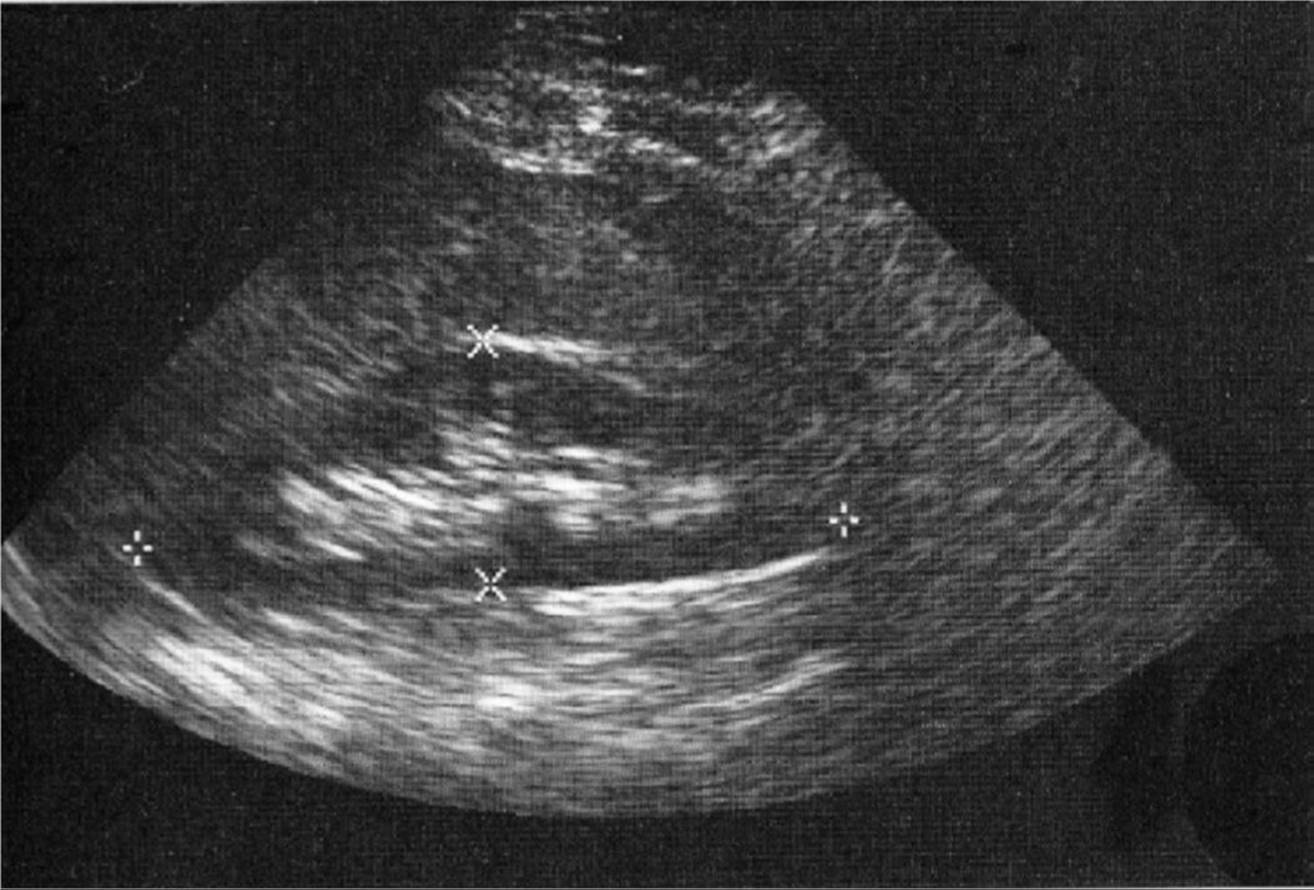

If the portal vein is acutely thrombosed, it will be dilated with acoustically homogeneous echoes within the lumen (Fig. 11–33). The thrombotic process may be segmental with sparing of one or more of the main tributaries.5Chronic thrombosis may cause the portal vein and its branches to be difficult to visualize because of a decrease in vein diameter and the presence of increased intraluminal echogenicity resulting from fibrosis.

FIGURE 11–33. Real-time image demonstrating acute thrombus within the lumen of the portal vein.